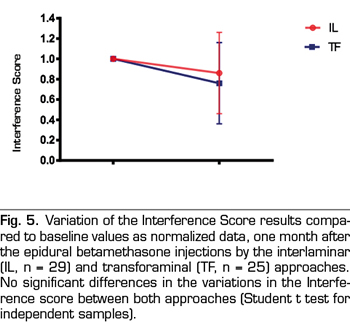

Intensity and Interference Scores were also reduced by the epidural steroid injection (Figures 4 and 5). Betamethasone administered by the parasagittal interlaminar approach produced a statistically significant reduction of the Intensity Score from 7.2 ± 1.2 to 5.8 ± 2.1 and the Interference Score from 7.0 ±1.8 to 5.8 ± 2.5 (p = 0.002 and p = 0.01, respectively; Student t test of paired samples). Betamethasone administered by the transforaminal route decreased the Intensity Score from 7.7 ± 1.6 to 5.7 ± 2.4 and the Interference Score from 7.7 ± 1.7 to 6.3 ± 3, statistically significant reduction (p = 0.0002 and p = 0.008, respectively). No statistically significant differences were found between both approaches when comparing the reduction of both scores.

When the changes in the VNS and the Interference Score of those patients whose responses were considered positive using betamethasone interlaminar or transforaminal (11 and 16, respectively) were compared, no differences were found for any of these parameters (Figures 6 and 7).